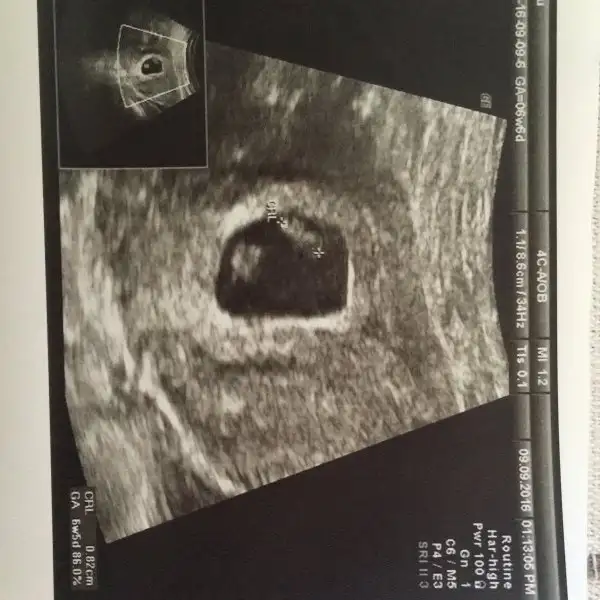

Merhabalar, bu başlığı birkaç haftadır takip ediyordum. Usg görüntümüzü paylaşmak için 8.haftamızı bekliyordum. Hamile olduğunu öğrenen her anne adayı gibi evvela sağlıklı ve hayırlı bir evlat olmasını niyaz ediyorum Rabbimden ama insan merak da ediyor tabii :))

Iki adet usg görüntüsü paylaşıyorum; birinde miniğimiz 6+1 diğerinde ise 8+0

Cinsiyet tahminlerinizi ve güzel dualarınızı heyecanla bekliyorum hanımlar, sevgiler ^.^

Ufak bir düzeltme: Sevgili @slvester, ben bu mesajı yanlışlıkla genital nub ile ilgili başlığa yazmış oldum ama sanırım haftamız itibariyle doğru yer burası ^.^

Siz ve diğer tüm arkadaşların tahminlerini merakla bekliyorum ^.^